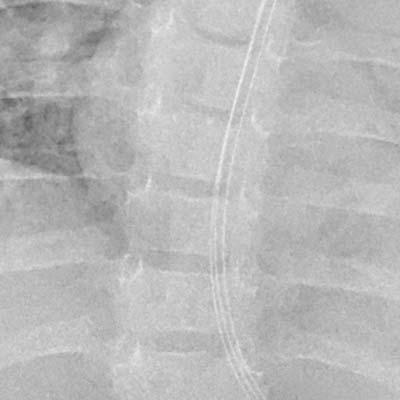

Référence : Comparaison des effets de réduction du bruit lors de l’utilisation de la réduction du bruit intelligente

1. Images capturées à l’aide d’un outil d’évaluation des performances des systèmes de diagnostic par rayons X (Burger Phantom)

Aucun traitement

Traitement conventionnel

NR intelligent